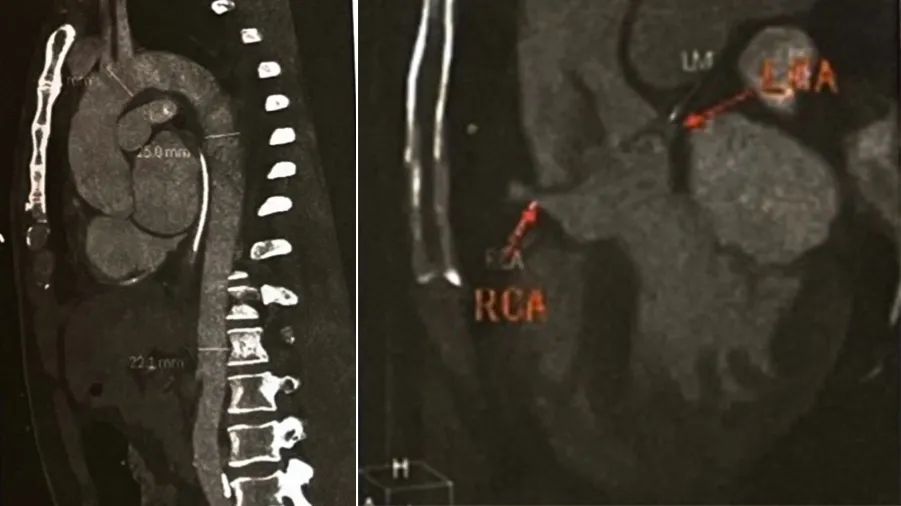

根据患者进一步检查结果,患者病史、体征、心脏超声结果基本同入院,但追要外院冠状动脉造影图像并仔细阅读后,存在以下特点:①主动脉瓣大量反流,与心脏超声检查不符合;②左主干开口局限狭窄;③右冠状动脉造影过程中随心动周期造影导管呈较大角度摆动扭曲,呈典型“死亡芭蕾征”导管影像特征。结合上述三点,考虑患者主动脉A型夹层累及双侧冠状动脉开口及主动脉瓣。病情不稳定,但明确病因迫在眉睫,取得患者风险同意后完善血管增强CTA检查(图4)。

图4:大血管增强 CT主动脉窦部至升主动脉近端可见内膜片影,内膜片撕裂,摆动进入左主干腔内,开口部分狭窄,右冠状动脉开口与内膜片紧邻,开口无狭窄,但有遮挡